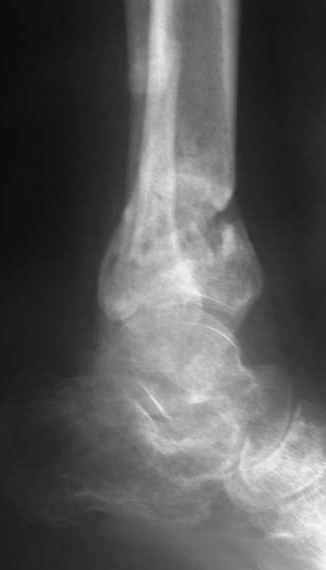

A 56 year old laborer fell off a wall approximately 5 months ago. He sustained an open pilon fracture. He was treated with debridement and external fixation. After he was treated for 4 months, the external fixator was removed.

The patient had no medical insurance and was therefore transferred to my care by his treating surgeon. He has remained NWB. He denies pain in his ankle. He has painless dorsiflexion and plantarflexion of his ankle joint.

I have attached his x-rays. I have also attached an WMV movie file of his axial CT (if you are unable to view this, I can post an MPEG file).

It seems to be a definite nonunion from the plain XRs.

The subtalar joint looks okay from what we can see on the lateral x-ray so I wouldn't want to damage it if it can be avoided. If thorough workup (WBC, ESR, CRP) shows no evidence for infection, he's a nonsmoker (or has quit) and there's no sign of infection at surgery, I would try a "moderately invasive" ORIF with debridement and autologous bone grafting. I think with a precontoured plate with locking screw capability one could get adequate fixation distally to allow immediate ROM and provide compression across the fracture.